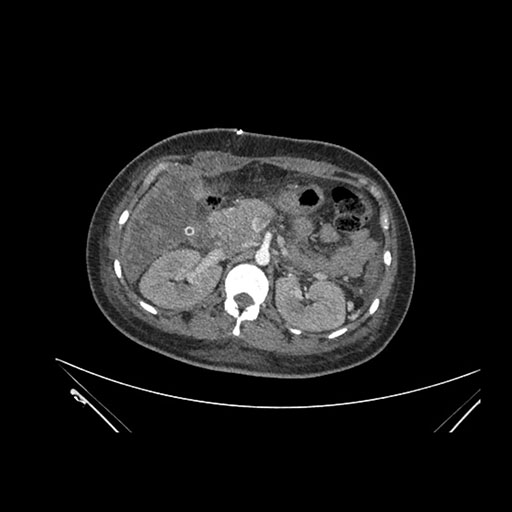

Axial Arterial

Axial Venous

Imaging analysis

Based on initial findings, which issue(s) would you be most concerned about?